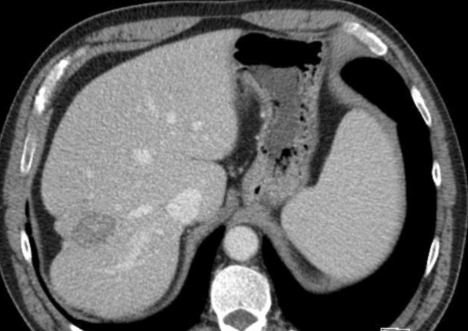

肝包膜皱缩除了胆管细胞癌还有这几种情况